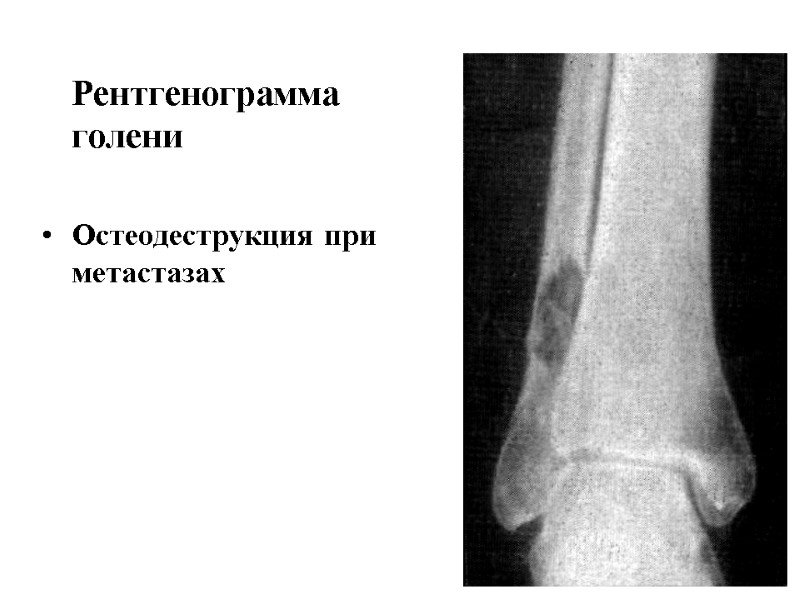

Рентгенограмма голени Остеодеструкция при метастазах